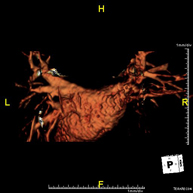

- Abdominal aorta MRI angiography

A non-invasive diagnostic test that involves studying the abdominal aorta, obtaining high-definition anatomical images using an electromagnetic field and radio waves (with transmitter and receiver). The use of paramagnetic contrast (gadolinium) is essential. However, it is a radiation-free procedure. The quality of the images allows for 2D and 3D reconstructions. It is indicated in patients with vascular disease (atherosclerosis), aneurysm studies, pre-surgical studies of lesions adjacent to the abdominal aorta as a vascular ‘map’, etc.